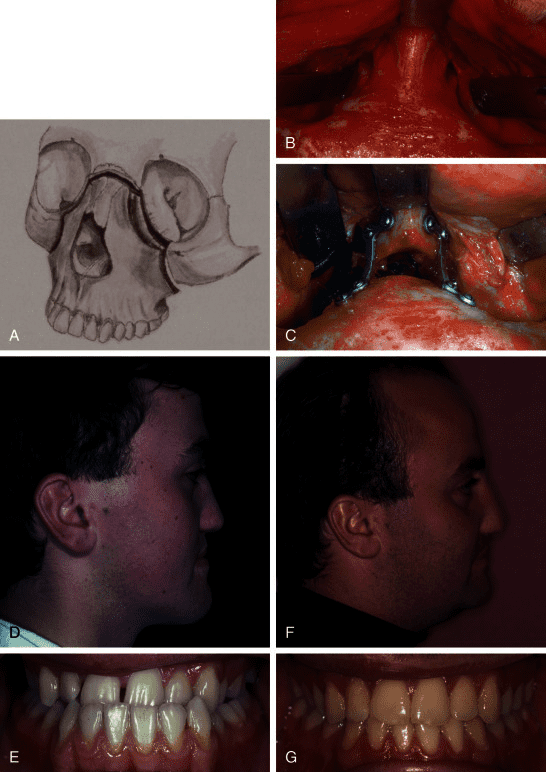

It moves cheekbones upward, give so much under eye support and even change orbital shape. Also widen face and change gonial angle. Is it modified lefort 3?